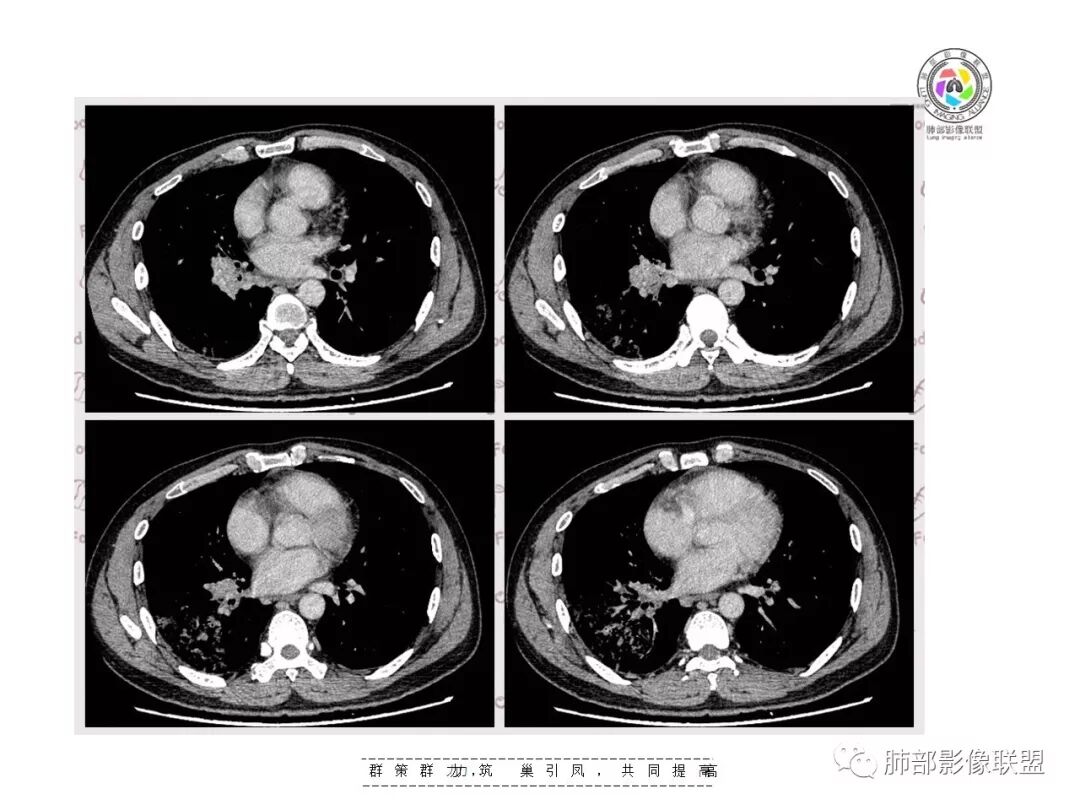

【影像资料】

右肺门区淋巴结增大,融合,密度均匀,均匀强化

符合这个特点的:结核?淋巴瘤?转移瘤?

淋巴结我觉得目前的特点:淋巴瘤?结核?

因为没有发现特异性征象,难以鉴别

单纯淋巴结结核比较少

复查胸部CT视频显示肺部病灶明显吸收,淋巴结较前缩小。

患者在本院做了支气管镜,报告是有新生物,取了活检就转院了。病理结果是后来出来的。去肿瘤医院再做支气管镜,病理还是炎症。抗炎治疗(电话追问患者家属,具体不详)一个月后复查,右下肺病变基本吸收,肺门肿块明显变小;纵隔淋巴结基本都没了或者明显变小了

我一直以为是二元的,我觉得特别淋巴结里面又有钙化灶,我的想法肺部就是炎性病变,因为很典型的分布符合气道来源炎性病变,但是淋巴结是独立出来的,里面有钙化灶怀疑结核可能。

淋巴结同步缩小了,其实挺常见的

如果看片考虑二元论,肺部符合急性炎性病变特点。淋巴结真不好说,一元论还没想通,也有存在特异性的可能,比较少。我就这样分析的,写报告我会写二元,把淋巴结独立出来,把右下肺急性炎症独立出来。

南边:当时看淋巴结该不该一元论?一元论该怎么考虑?因为右下肺病变确实没有恶性特点,所以还是考虑二元论。因为薄层CT确实有点状钙化,当时考虑结核可能性大,淋巴结确实涉及少了。